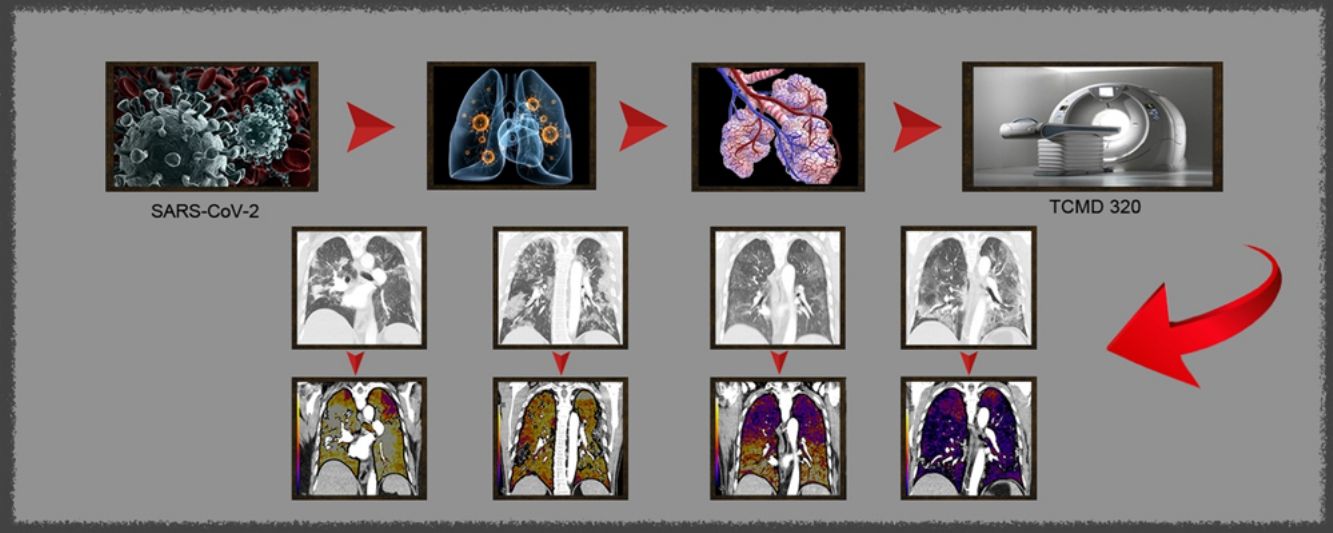

La enfermedad por coronavirus COVID-19, surgida en Wuhan, China en diciembre del 2019 y causada por el virus SARS-CoV-2, en tres meses se ha convertido en una pandemia1,2 tal y como ha sido declarado por la Organización Mundial de la Salud el 11 de marzo de 2020.

Las angiografías pulmonares se realizaron en un TCMD Aquilion ONE (Canon Medical Systems) con software V8.3 release SP9004G, con mapa de yodo (en escala de color) mediante técnica de sustracción avanzada. El contraste empleado fue Ultravist® 370 mg/mL (60-80 mL a 4,5 mL/s, seguido de 40 mL de suero salino) y se adquirió la angiografía con bolus tracking, colocando el ROI (region of interest) en aorta ascendente con umbral de 100 UH. La adquisición se realizó en dirección craneocaudal con 120 kV, ajuste estándar de la dosis con control de exposición automático (60-80 mA) y pitch de 0,8.